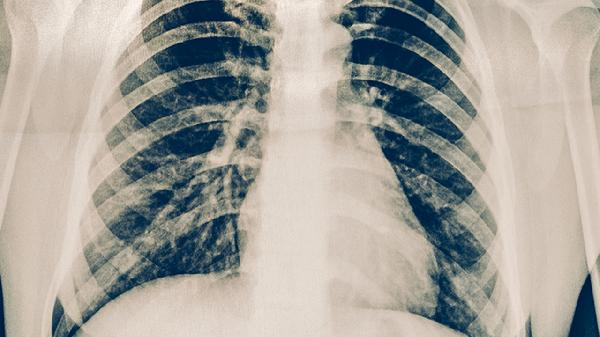

建议骨折稳定后再考虑双眼皮手术,术前需完善胸片检查确认愈合情况。术后保持高蛋白饮食促进骨骼与伤口修复,适量补充维生素D和钙质。恢复期避免剧烈运动及胸部受压,睡眠时采用45度仰卧位减轻肿胀。眼部护理需严格遵循无菌原则,定期复查骨折与伤口愈合进度。